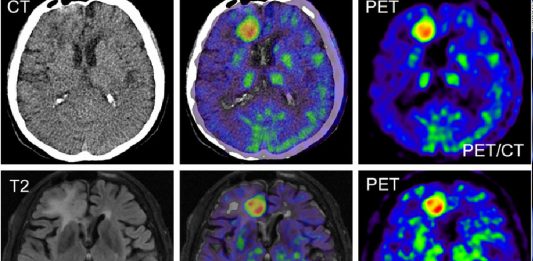

Acil Serviste Nöroradyolojik Görüntüleme

Özellikle son 20 yıldaki teknolojik gelişmelerden en çok elektronik ve bilgisayar alanındakiler tıpta yeni ufuklar açmıştır. Tüm görüntüleme yöntemlerinin temelini oluşturan bu alanlardaki gelişmeler de doğal olarak radyoloji ve nöroradyolojide çok büyük değişimlere ve gelişmelere yol açmıştır. Ayrıca son yıllarda tüm dünyada tıbbi ilerlemelerle hastalıkların patofizyolojileri hakkında daha fazla bilgi sahibi olunması ve acil servislerdeki … Acil Serviste Nöroradyolojik Görüntüleme okumayı sürdür